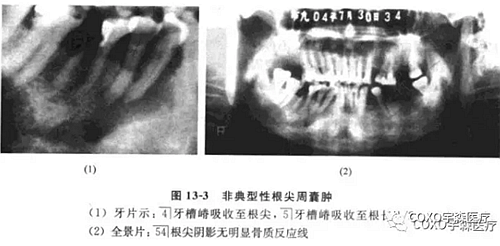

(二)非典型性根尖周囊腫根尖周囊腫的診斷除臨床癥狀外,主要靠X線片檢查。經(jīng)典的診斷標(biāo)準(zhǔn)應(yīng)為在相應(yīng)患牙的根尖部呈現(xiàn)界限清楚的圓形骨質(zhì)稀疏的透射陰影。

周邊可有不同程度白色骨質(zhì)反應(yīng)線;但是不應(yīng)忽略有時(shí)根尖部 線區(qū)表現(xiàn)可以呈非典型性。

病例:女性,72歲,右下牙齦腫脹3周,有牙痛史,外院拍片診斷為“根尖周囊腫”并行頰側(cè)組織切片檢查,病理診斷為“炎癥性病變”轉(zhuǎn)來我院。

檢查:54]頰側(cè)骨膨隆,頰側(cè)活檢切口無膿性分泌,54]無松動(dòng),無叩痛,6]殘冠、x線片示:654]]冠部均有充填物,4]牙槽骨吸收已近根尖,51]牙槽骨吸收至根長1/2。全景片示:54]根尖陰影,無明顯骨質(zhì)反應(yīng)線(圖13-3),54]電活力測試無反應(yīng)。

本病例的臨床診斷為根尖周囊腫,似無太大疑問,但X線表現(xiàn)則十分不典型:54]根尖骨質(zhì)呈不規(guī)則、潛穴性吸收,底部幾達(dá)顏孔,更無明顯骨質(zhì)反應(yīng)線。由于54]無明顯松動(dòng)及叩痛,加之頰側(cè)骨質(zhì)膨脹,致使牙體牙髓病醫(yī)師疑為腫瘤,不敢進(jìn)行根管治療術(shù)。手術(shù)結(jié)果證實(shí)仍為根尖周囊腫伴反應(yīng)性骨質(zhì)增生。結(jié)合術(shù)中見病灶區(qū)有大量肉芽組織,說明本病例的炎癥過程可能持續(xù)時(shí)間較長,程度較重,致使 線片表現(xiàn)呈不典型性。本例的經(jīng)驗(yàn)是:應(yīng)牢記根尖周囊腫還有不典型表現(xiàn)者,臨床應(yīng)綜合各方面的因素考慮,方能更進(jìn)一步提高臨床診斷水平。